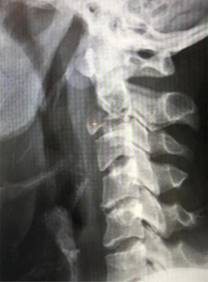

En las radiografías cervicales simples se observó una lesión expansiva, geográfica, circunscrita al cuerpo vertebral de C2; asimismo, se apreció una lesión en T1 con las mismas características de la lesión previamente descrita (Figura 1). En la tomografía axial computarizada (TAC) se observó una lesión hipodensa circunscrita en el cuerpo vertebral de C2, expansiva, que se extendía desde la base del cuerpo vertebral hasta la porción superior de la odontoides, además, se detectó una lesión hipointensa, circunscrita, de bordes regulares en el cuerpo vertebral de T1 (Figura 2).